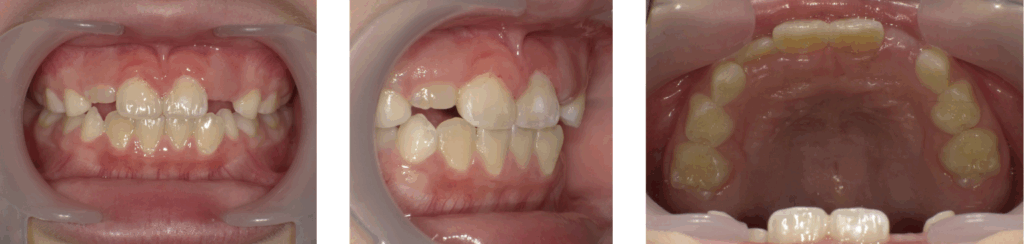

症例1:急速拡大装置とブラケット装置を併用した矯正治療

| 年齢 | 8歳 |

| 性別 | 女子 |

| 治療の理由(主訴) | 前歯がねじれていて、すきっ歯が気になる。 見た目をきれいにしたい。 |

| 治療方法 | 顎顔面矯正+ワイヤー矯正 |

| 治療期間 | 1年10か月 |

| 費用 | 66万円 |

治療前